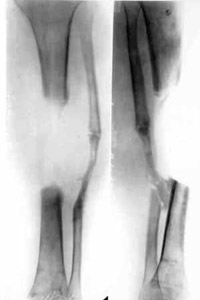

Defect of middle/third of spin-bone. | |